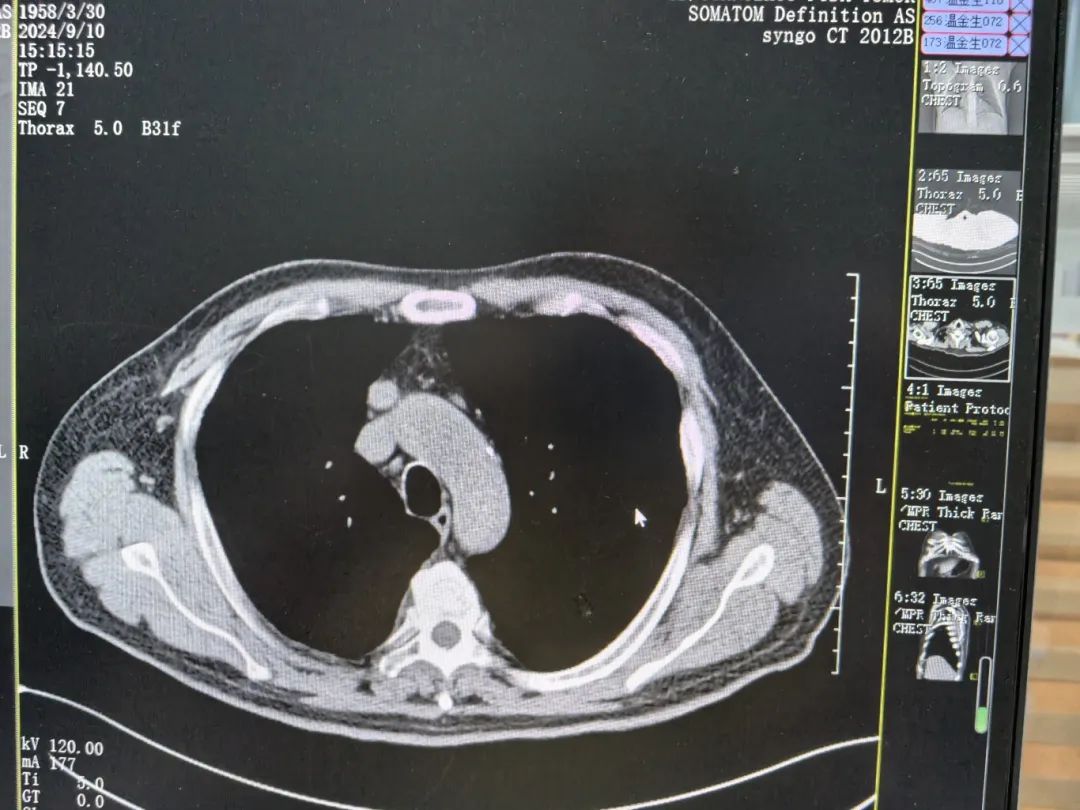

接受一次粒子植入以及三四次介入和免疫治疗后,金叔真心觉得当初的“直觉”是对的。一次次的疗程,一次比一次好,CT结果显示,金叔的右肺肺门区病灶明显缩小,纵膈部分肿大淋巴结以及双肺部分结节较前缩小。多次住院经历,让金叔在复大有了从未有过的良好就医体验。

▲治疗两月后影像结果